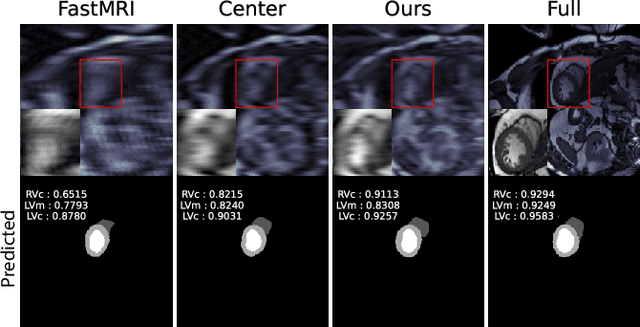

To accelerate MRI, the field of compressed sensing is traditionally concerned with optimizing the image quality after a partial undersampling of the measurable $\textit{k}$-space. In our work, we propose to change the focus from the quality of the reconstructed image to the quality of the downstream image analysis outcome. Specifically, we propose to optimize the patterns according to how well a sought-after pathology could be detected or localized in the reconstructed images. We find the optimal undersampling patterns in $\textit{k}$-space that maximize target value functions of interest in commonplace medical vision problems (reconstruction, segmentation, and classification) and propose a new iterative gradient sampling routine universally suitable for these tasks. We validate the proposed MRI acceleration paradigm on three classical medical datasets, demonstrating a noticeable improvement of the target metrics at the high acceleration factors (for the segmentation problem at $\times$16 acceleration, we report up to 12% improvement in Dice score over the other undersampling patterns).